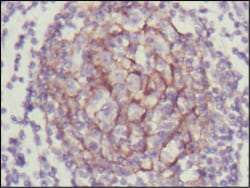

分类: 科研抗体货号: 20345别名: Isl-1; ISLET1应用: IHC,IF反应种属: Human,Mouse,Rat,Rabbit

分类: 科研抗体货号: 20344别名: Isl-1; ISLET1应用: IHC,IF反应种属: Human,Mouse,Rat,Rabbit